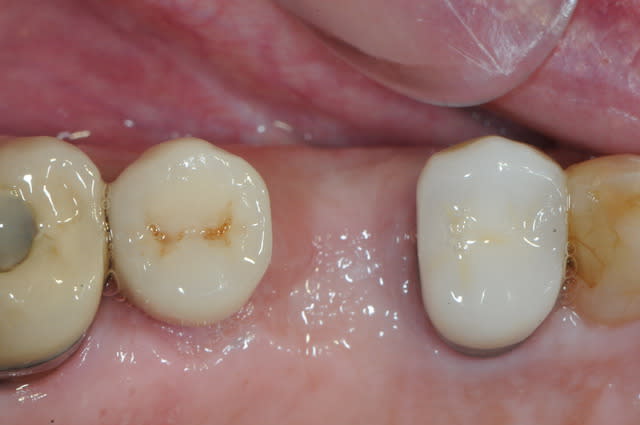

ton intervention, albert, me rappel un cas clinique que j'aimerai partager avec vous:

1-2-3 prémolaire foutu juste à proximité d'un implant, faut donc faire gaffe aux tissus environnant.

en plus je suis sure que la corticale vestibulaire est K.O elle aussi.